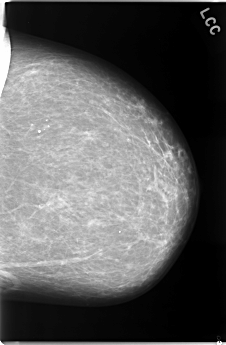

C_0083_1.RIGHT_CC

RIGHT_CC LINES 5928 PIXELS_PER_LINE 3720 BITS_PER_PIXEL 12 RESOLUTION 50 NON_OVERLAY